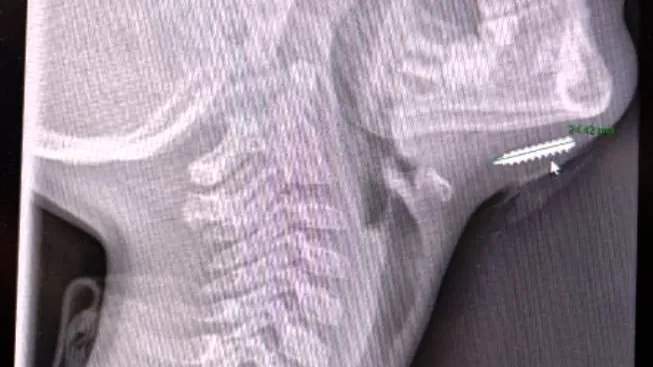

ד"ר בשיר נסראללה, מומחה ברפואה דחופה בילדים במרכז הרפואי בני ציון, ביצע בדיקת אולטרסאונד ליד מיטת הילד (POCUS) אשר העלתה חשד לגוף זר בעומק הרקמה. צילום רנטגן שבוצע מיד לאחר מכן חשף את ההפתעה: בורג קטום באורך של כשני סנטימטרים היה נעוץ בתוך סנטרו של הילד.

פרופ' יעקב גניזי, מנהל מחלקת ילדים במרכז הרפואי בני ציון, סיפר על הפעולה: "בפעולה מתואמת עם מומחי אף־אוזן־גרון במרכז הרפואי בני ציון הוצא הבורג בשלמותו, ולאחר מכן נתפר הפצע."